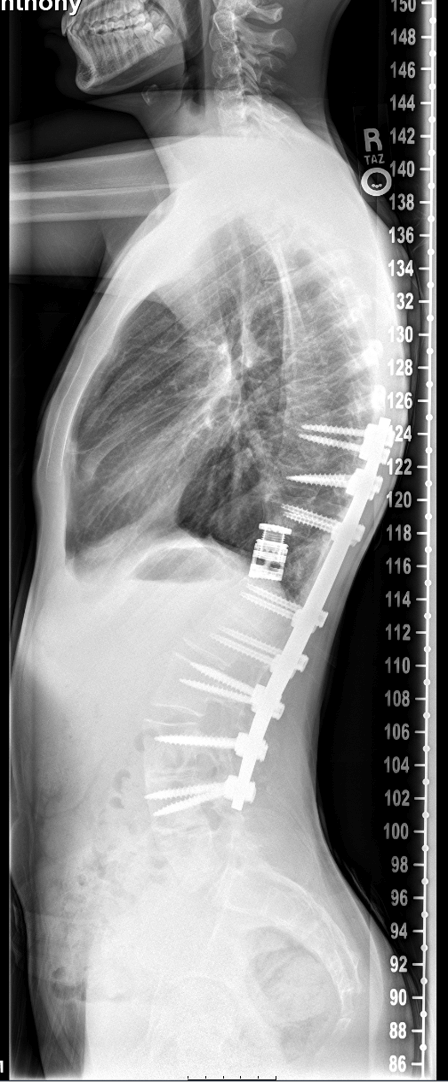

Post-surgery radiographs after complete resection of the abnormal bone from around the spinal cord and replaced with a metal cage, with the kyphosis corrected and stabilized with spinal instrumentation.As for results, the patient was discharged from UH Rainbow a week after surgery. Just two months after that, he was playing trumpet with his high school marching band. He has returned to all of his activities and is pain-free.